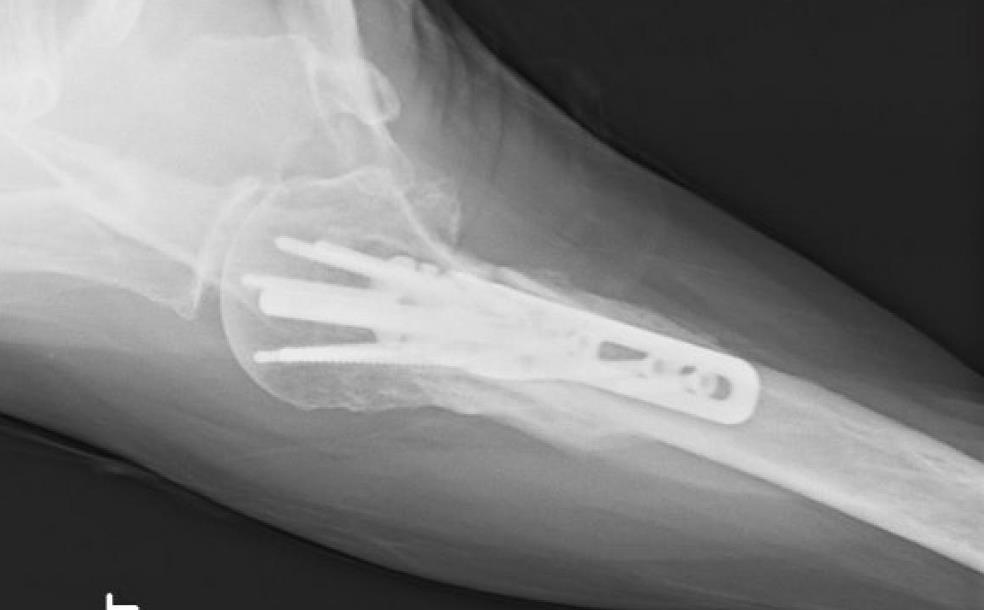

Proximal Humerus Fixation System

• The Proximal Humerus Fixation System (PHFS) from Skeletal Dynamics is a plate-and-peg/screw construct designed around proximal humeral anatomy for fixation of fractures, fracture-dislocations, osteotomies, and non-unions of the proximal humerus.

• The system centers on a proximal humerus plate with smooth locking pegs, locking/compression screws, and a central fixed-angle peg, with both straight and curved plate options.

• A side-specific plate (left or right) is selected, choosing straight or curved geometry and appropriate length based on the fracture pattern and need for distal fixation.

• The proximal plate is positioned 2.5–3.0 cm distal to the tip of the greater tuberosity.

• The anterior straight border of the plate is aligned just lateral to the bicipital groove, aligning the metaphyseal peg trajectories through the humeral head and maintaining space for the biceps tendon.

• FreeFix 4.5 mm compression screws are typically used in oblong slots to compress the plate to the bone and allow small translational adjustments.

• Once plate position is finalized, 4.5 mm FreeFix locking screws are inserted into round holes to provide fixed-angle diaphyseal support.

• Final fluoroscopy confirms reduction, peg and screw lengths, plate height relative to the greater tuberosity, and absence of joint penetration or subacromial impingement risk.